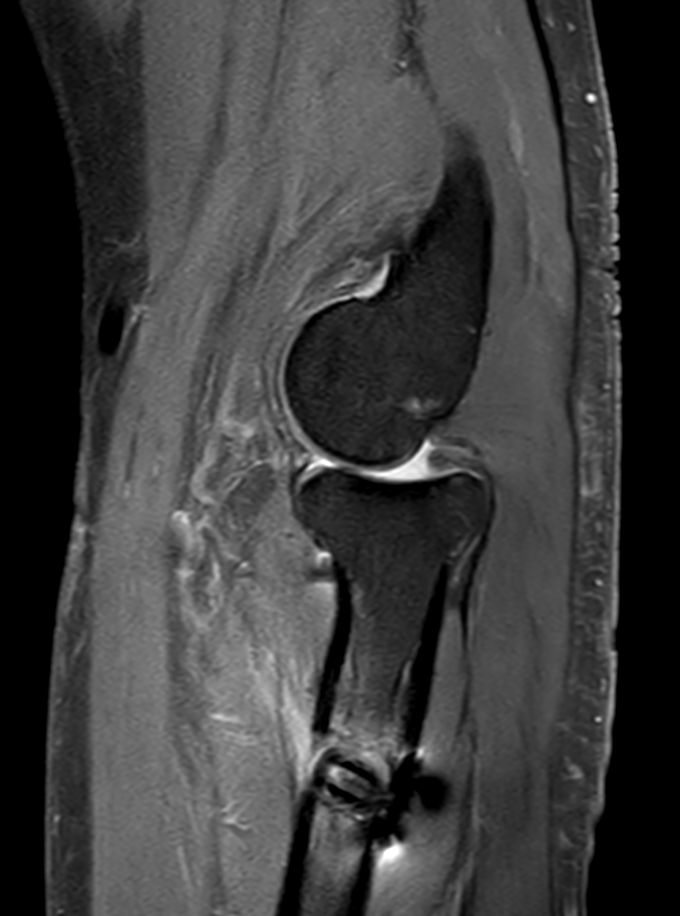

PDw TSE FatSat Compressed SENSE

T1w TSE Compressed SENSE

T2w TSE MultiVane XD FatSat